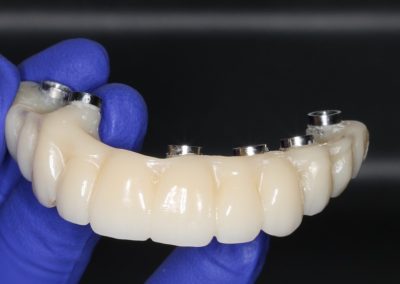

Uno de los aspectos más destacados fue que, en el mismo acto quirúrgico, se realizó la toma de la impresión para enviar a confeccionar una estructura provisoria completa (con la totalidad de los dientes maxilares), diseñada y elaborada mediante un proceso digital, lo que permite acortar tiempos y aumentar la precisión en etapas clave del tratamiento.